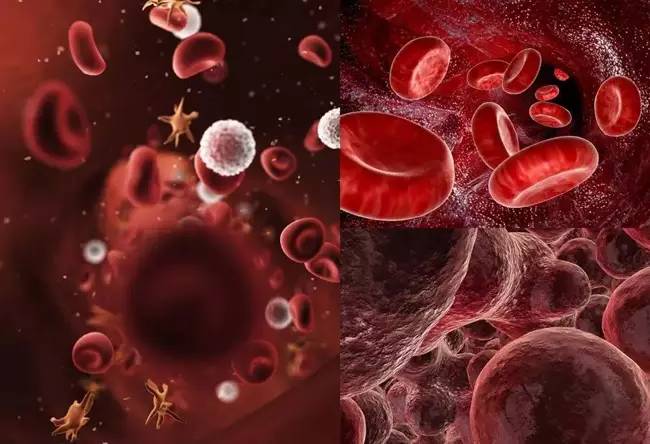

我们身体的血液每时每刻处在环境污染、各种细菌、病毒以及我们自身代谢废物的重重“包围”之中,如果这些侵害突破了我们机体的免疫“防线”或者累积过多,就会造成血液成分的改变,通俗来说,就是血液“变脏”。那么,血液为何会“变脏”?血液“变脏”又有哪些害处呢?

工业污染物如重金属、苯、甲醛、氟等进入人体,可引起白血病、再生障碍性贫血、高铁血红蛋白血症、氟中毒等多种严重危害人类健康的疾病,细菌、病毒、寄生虫的侵袭,还会引起肝炎、痢疾、艾滋病、疟疾、结核病、钩虫病、血吸虫病等传染病和寄生虫病的肆虐。血液不再“纯净”,必将引发全身性疾病的滋长。

现代医学研究证实,人的血液中含有大量自由基、化学残留物、重金属粒子、血锈等毒素和脂肪颗粒等废物,这些毒素、废物和杂质、内源性垃圾等总称为血毒。

从婴儿一出生,血液里就开始产生毒素。随年龄增长,血毒越积越多。30多岁时,血毒已有1500克。 血毒有10000多种,其中以饱和脂肪、坏胆固醇、自由基三种血毒对人体伤害最大,它们是:过量的总胆固醇(TCHO)、甘油三酯(TG)、低密度脂蛋白(LDL-C)、自由基、尿素、尿酸、血肌酐,大量产生的酸性物质(碳酸、硫酸、磷酸、乳酸、丙酮酸等)、胍类多胺,以及铅、砷、汞、硫、铝、亚硝酸盐等危险化学成分。

血液净化疗法,通过激活免疫细胞,产生一种非特异性脱敏作用,促进白细胞吞噬能力,从而增强机体免疫力,灭菌排毒,重建身体健康的生态环境。

血液净化疗法,能够通过减少血液中的红细胞凝聚,提高其携氧能力和改善血流变,增加血液对组织的供氧量,改善机体的代谢状态,使之达到正常的平衡状态。

每个人的血液中的物质都不同,在血液净化的过程中,排出来的血液无论在颜色、密度、沉淀物等方面都是因人而异的。健康的人群排出来的血液与净化后的血液是差不多的,但身体有问题的血液差别就非常大,血液的颜色有黑色的、暗红色的,甚至有乳白色的,如果有脂肪肝的甚至会排出一条条的脂肪,有些客户的血液会特别粘稠特别黑,有些有坏死的血红细胞排出来时,血液又特别的鲜红……